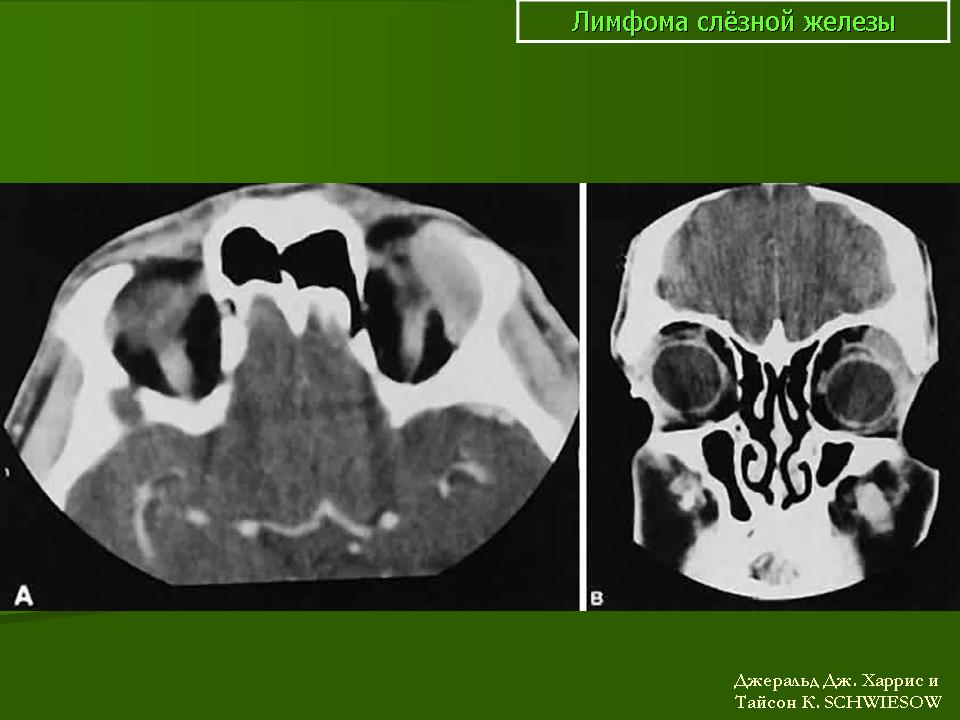

Злокачественная лимфома (неходжкинская) по частоте в последние годы выходит на одно из первых мест среди первичных злокачественных опухолей орбиты. В орбите опухоль чаще развивается на фоне аутоиммунных заболеваний или иммуноде-фицитных состояний. Мужчины болеют в 2,5 раза чаще. Средний возраст заболевших 55 лет. В настоящее время злокачественную неходжкинскую лимфому рассматривают как новообразование иммунной системы. В процесс вовлекаются преимущественно лимфоидные элементы Т- и В-клеточной принадлежности, а также элементы нулевых популяций. При морфологическом исследовании в орбите чаще диагностируют В-клеточную лимфому низкой степени злокачественности, в которой содержатся достаточно зрелые опухолевые и плазматические клетки. Как правило, поражается одна орбита. Характерны внезапное появление безболезненного экзофтальма, чаще со смещением глаза в сторону, и отек периорбитальных тканей. Экзофтальм может сочетаться с птозом (рис. 20.24, а). Процесс местно неуклонно прогрессирует, развивается красный хемоз, становится невозможной репозиция глаза, возникают изменения на глазном дне, чаще застойный диск зрительного нерва (рис. 20.24, б). Резко снижается зрение. В этот период могут появиться боли в пораженной орбите.

Диагноз злокачественной лимфомы орбиты труден. Из инструментальных методов исследования более информативны ультразвуковое сканирование, компьютерная томография (рис. 20.24, в) и тонкоигольная аспирационная биопсия с цитологическим исследованием. Необходимо обследование у гематолога для исключения системного поражения. Наружное облучение орбиты — практически безальтернативный высокоэффективный метод лечения. Полихимиотерапию подключают при системном поражении. Эффект лечения проявляется в регрессии симптомов патологического процеса в орбите и восстановлении утраченного зрения. Прогноз при первичной злокачественной лимфоме для жизни и зрения благоприятный (83 % больных переживают 5-летний период). Прогноз для жизни резко ухудшается при диссеминированных формах, но частота поражения орбиты при последних составляет чуть более 5 %.